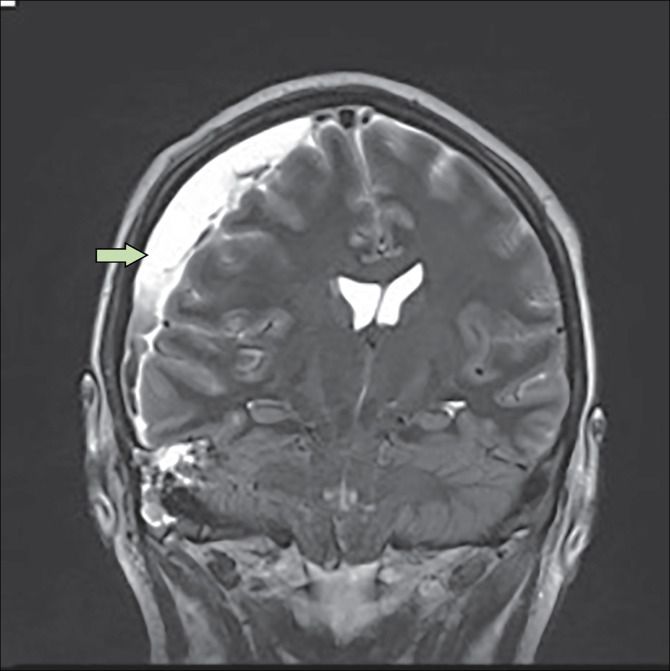

Subdural empyema refers to collection of pus between dura and arachnoid mater. It is an intracranial abscess. The consequences includes focal neurological deficits secondary to extrinsic pressure and inflammation of brain and meninges. The patient with subdural empyema typically gives history of prior airway infection, otitis media, or sinusitis. Seizures, high grade fever, confusion, vomiting, and amblyopia are common complaints. Management includes stabilization of patient, antibiotics, and surgical drainage. Reference: https://emedicine.medscape.com/article/1168415-treatment#d6 Image via: https://www.thelancet.com/journals/laninf/article/PIIS1473-3099(18)30096-3/fulltext